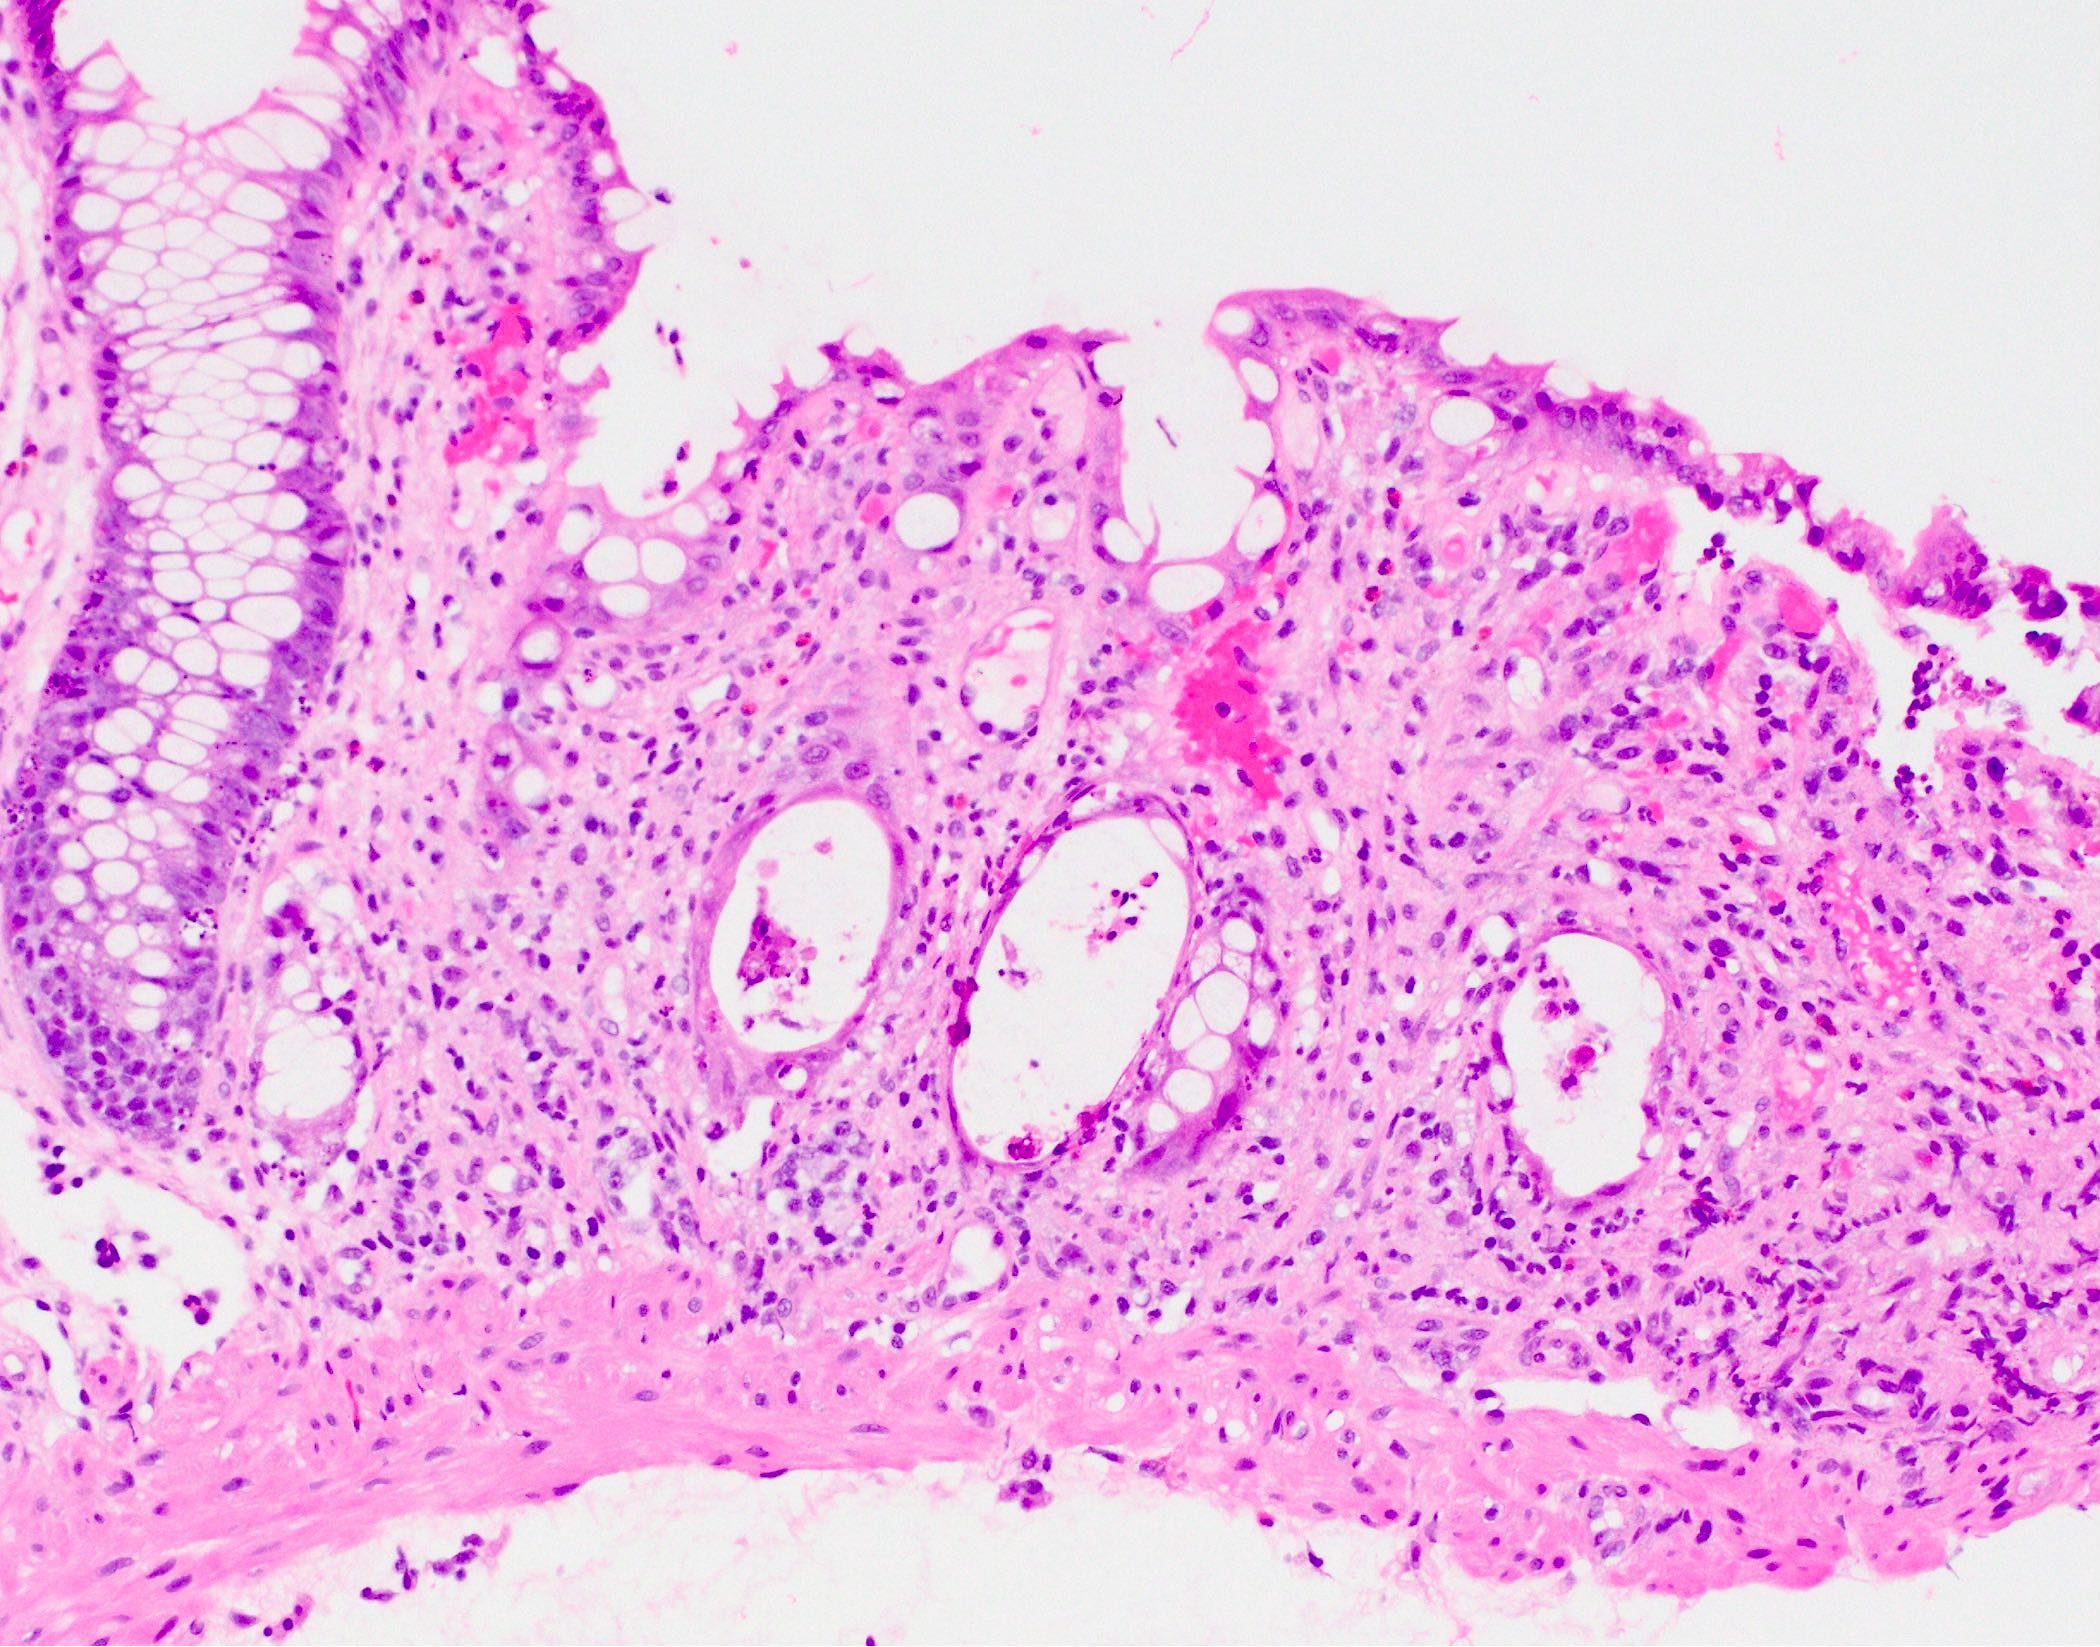

- Characteristic histologic features include crypt apoptosis, crypt dropout and ulceration (Biol Blood Marrow Transplant 2015;21:589)

- Inflammation is generally sparse

- Endocrine cell nests may be seen (Am J Surg Pathol 2013;37:1319)

- Fibrosis and crypt architectural changes are markers of longstanding disease but not specific features of chronic graft versus host disease (Am J Clin Pathol 2016;145:591)

- Apoptosis in the colon is not specific to graft versus host disease and the lower diagnostic threshold is debated

- National Institute of Health proposes ≥ 1 apoptotic body per biopsy fragment (Biol Blood Marrow Transplant 2015;21:589)

- Others propose > 6 apoptotic bodies per 10 contiguous crypts for definitive diagnosis of graft versus host disease (Am J Surg Pathol 2013;37:539)

- Cases with ≤ 6 apoptotic bodies per 10 contiguous crypts are considered indeterminate for graft versus host disease (Histopathology 2016;69:802)

- Utility of histologic grading is questionable because of poor correlation with patient outcome

- When grading is performed, the Lerner system is most commonly utilized

- Grade I: crypt apoptosis without crypt dropout

- Grade II: single crypt dropout

- Grade III: contiguous crypt dropout

- Grade IV: diffuse crypt dropout with ulceration

- When grading is performed, the Lerner system is most commonly utilized

- Graft versus host disease in autologous stem cell transplant patients shows more prominent crypt apoptosis but is otherwise histologically identical to allogeneic graft versus host disease (Mod Pathol 2018;31:1619)

- Histologic examination of at least 8 serial sections is recommended to avoid missing rare apoptotic bodies (Biol Blood Marrow Transplant 2015;21:589)

Microscopic (histologic) images